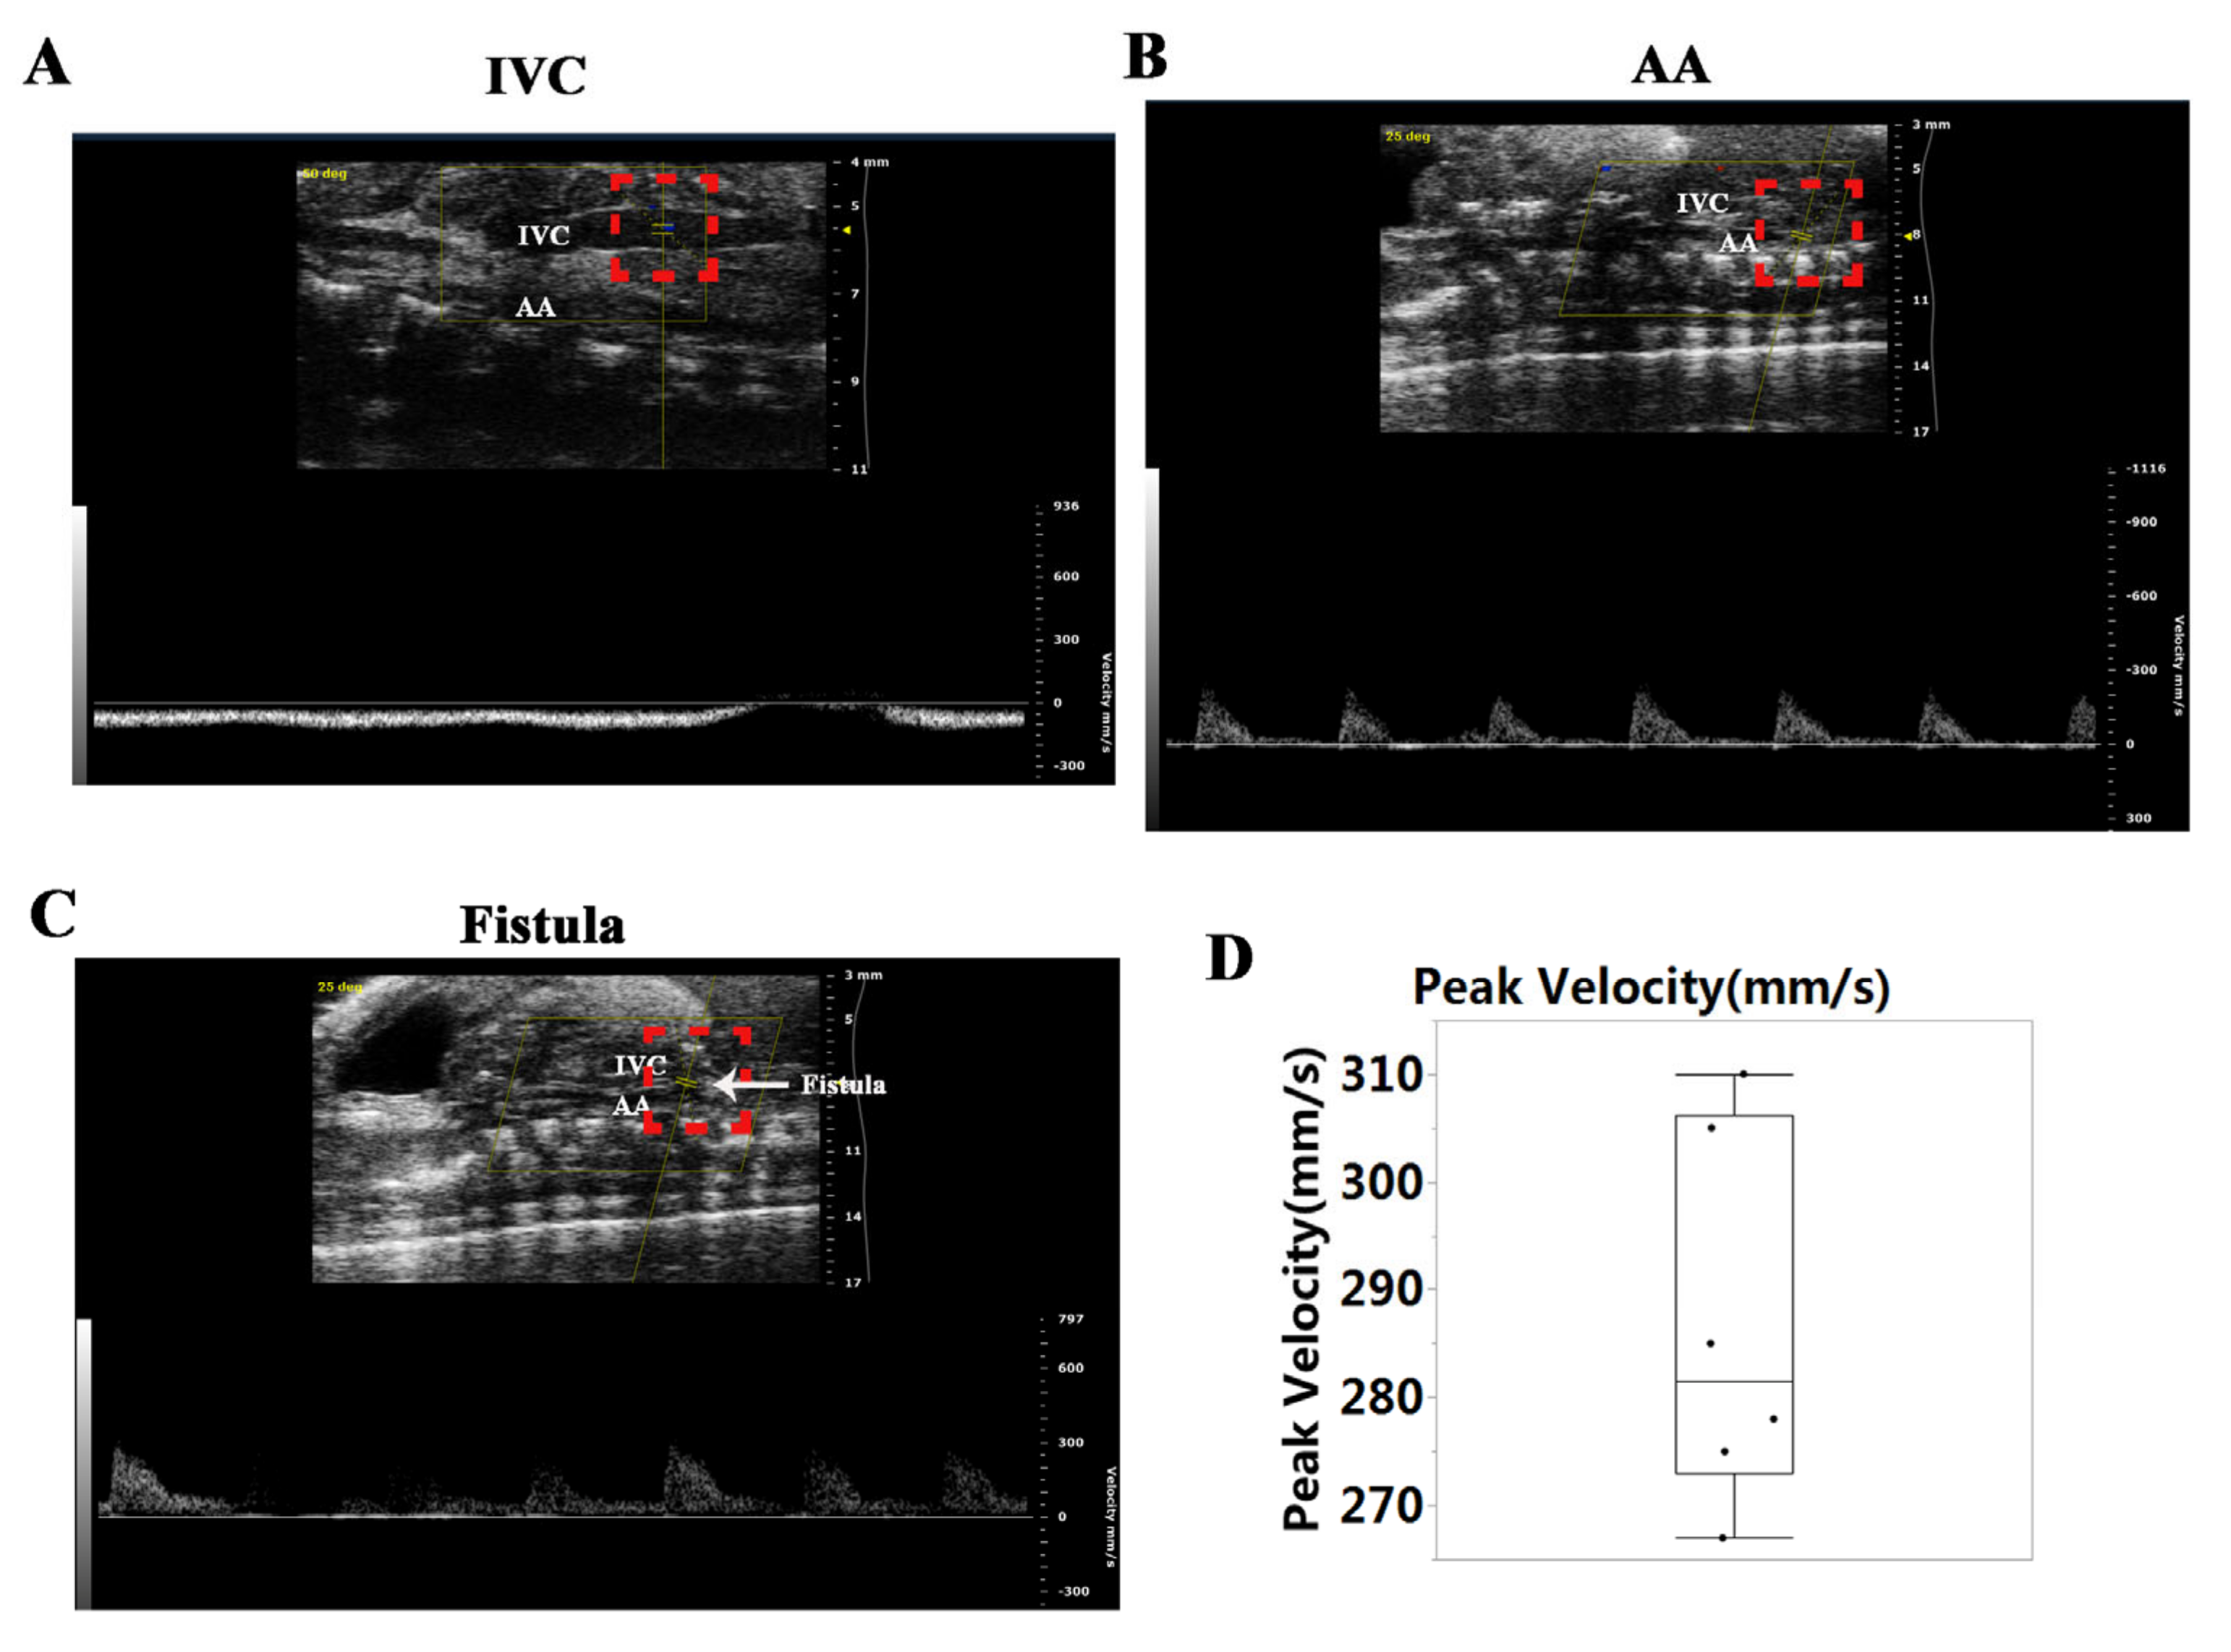

3.1. Establishment of Ventricular VO via AVF Surgery